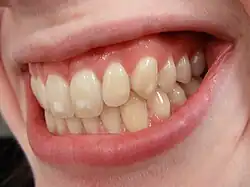

Dental fluorosis

Dental fluorosis is a dose-dependent adverse drug effect featured by temporary white marks.[5] It can be induced by increased fluoride exposure, typically from stannous fluoride-containing products or fluoridated water.[5][20] Excess intake of fluoride leads to overabundance of structurally-weak fluorapatite formed inside the enamel, resulting in increased brittleness of teeth.[21] In severe dental fluorosis, brown or yellow staining may appear on teeth.[8] Children under the age of eight are susceptible to dental fluorosis.[8]